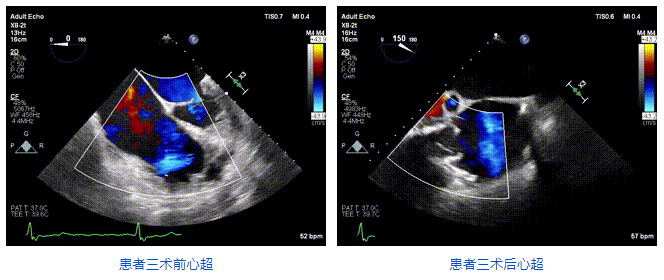

2021年12月24日,復(fù)旦大學(xué)附屬中山醫(yī)院葛均波院士團(tuán)隊(duì)成功應(yīng)用LuX-Valve Plus為一例極重度三尖瓣反流(TR)合并房顫、房缺的患者完成了經(jīng)血管三尖瓣置換術(shù),這是在前基礎(chǔ)上,本周完成的第三例經(jīng)血管三尖瓣置換手術(shù),葛均波院士、周達(dá)新教授等與心外科魏來教授、賴顥教授,心超室的潘翠珍教授、李偉教授及麻醉科的郭克芳教授共同完成了本周手術(shù),均獲得圓滿成功!患者術(shù)后超聲顯示無TR,臨床癥狀明顯改善。本周手術(shù)的成功也為L(zhǎng)uX-Valve Plus救治性臨床研究添上了濃墨重彩的一筆。

三例患者入院后,葛均波院士團(tuán)隊(duì)周達(dá)新教授、潘文志教授、張?jiān)床┦俊㈥惿┦考靶某业呐舜湔浣淌?、李偉教授?duì)患者的情況進(jìn)行詳細(xì)評(píng)估和討論,最終決定為三例患者選擇LuX-Valve Plus40mm、50mm和50mm型號(hào)的瓣膜進(jìn)行手術(shù)治療。手術(shù)后即刻拔除氣管插管,術(shù)后患者三尖瓣反流癥狀得到顯著改善,復(fù)查心超結(jié)果顯示人工三尖瓣瓣膜支架固定穩(wěn)定,瓣葉關(guān)閉形態(tài)未見異常,未見明顯反流。